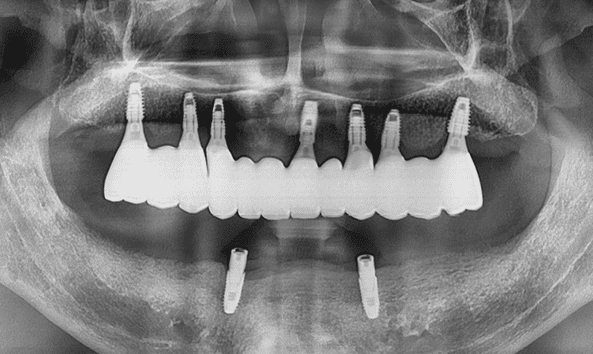

일반틀니 + 임플란트 틀니

전체 임플란트 + 임플란트 틀니

- 23.10

* 임플란트 시술 시 교합이상, 신경손상, 염증 등의 부작용이 발생할 수 있습니다.

* 개인의 구강 및 치아상태에 따라 치료방법과 수가가 변동될 수 있습니다.

* 해당 사례는 의료법 제56조 2항을 준수하여 작성되었습니다.

* 본원에서 진료받은 환자이며 전후 사진의 인물이 동일인임을 밝힙니다.